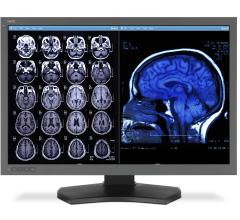

Siemens Healthcare announced the U.S. Food and Drug Administration (FDA) has cleared two new magnetic resonance imaging (MRI) applications – Simultaneous Multi-Slice (SMS) and GOBrain – designed to dramatically reduce the time required for MRI examinations of the brain.

Using a sophisticated magnetic resonance imaging (MRI) technique, researchers have found abnormalities in the brain’s white matter tracts in patients with insomnia.

April 26, 2016 — Repeated head impacts to high school football players cause measurable changes in their brains, even ...